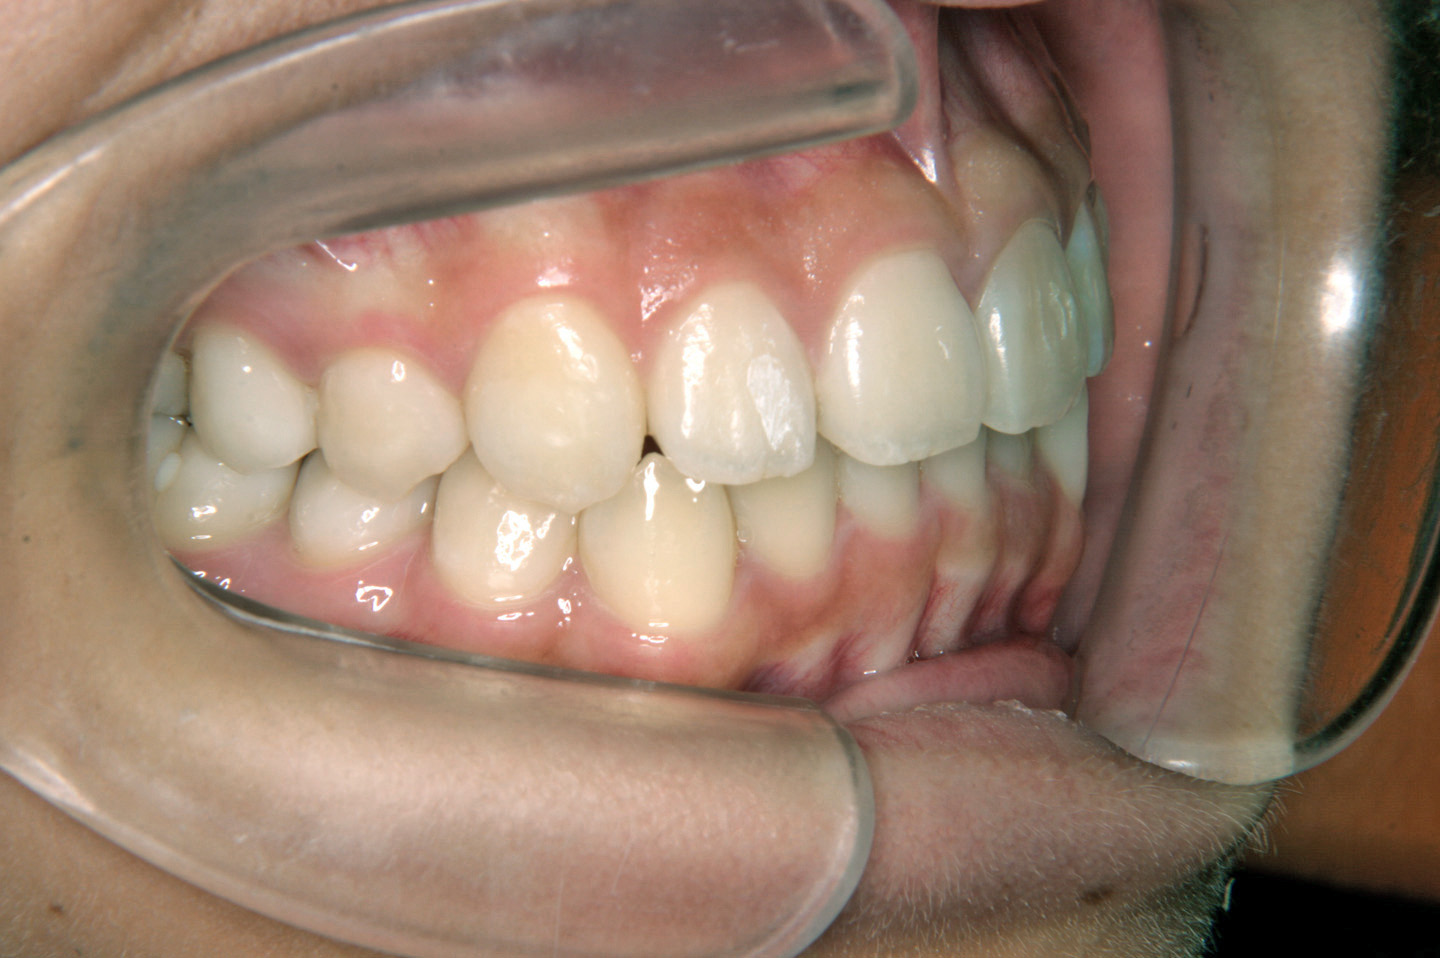

上の前から2番目の歯が内側から生えてきたことを気にされて来院されました9歳の女子です。前期治療としてリンガルアーチを用いて前歯の早期接触を改善し、その後、非抜歯での配列を目標としヘッドギアーで上顎大臼歯の後方への拡大を行いました。エッジワイズ装置(デーモンシステム)で後期治療を行っておりますが、非抜歯で、良好な結果を得ることができました。